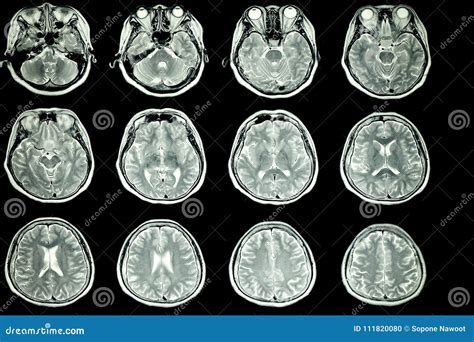

When you undergo this procedure, the radiologist evaluates several key components to ensure everything is within expected limits:

• Ventricular System: Examining the fluid-filled spaces of the brain to ensure they are the correct size and shape.

• White and Gray Matter: Ensuring the tissue density and distribution are consistent with healthy neural architecture.

• Brain Stem and Cerebellum: Checking for clear structures at the base of the brain responsible for vital functions.

Brain Tissue Symmetrical, distinct gray/white matter Asymmetry, lesions, or signal changes

Ventricles Normal size, no midline shift Enlarged, compressed, or shifted

Brain Stem Intact, clear boundaries Compression or abnormal signal

Signal Intensity Uniform and consistent Hyperintensities or "spots" (gliosis)